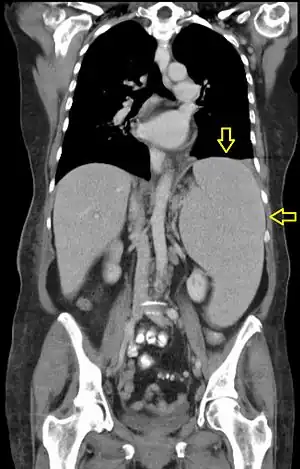

CT scan in a patient with chronic lymphocytic leukemia, showing splenomegaly. Yellow arrows point at the spleen.

Abdominal CT is the most accurate and spleen need to be larger 2-3 times to be palpable below the costal margin in physical examination that can help in diagnosis.